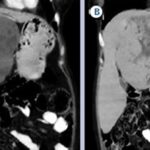

Hepatocarcinoma fibrolamelar

El carcinoma fibromelar hepatocelular es poco frecuente y representa menos de 1% de todos los casos. Se presenta principalmente en adolescentes y adultos jóvenes como una masa tumoral hepática única, con frecuencia de gran tamaño, sin asociación con cirrosis y rodeada de una cápsula fibrosa. En la tomografía multicorte, sin contraste, se observan tumores hipodensos heterogéneos con una cicatriz central muy hipodensa. También puede haber áreas de necrosis y calcificaciones. Son lesiones hipervasculares con captación intensa pero heterogénea (Anexo 15) del medio de contraste en fase arterial, la captación en fase portal y de equilibrio son variables y la cicatriz central, los septos y la cápsula del tumor son hiperdensos en fase tardía, incluyendo en los estudios de RM.(18-19)